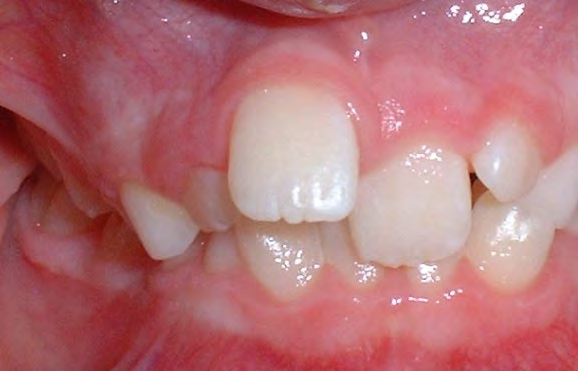

All of the patients below had been told they required extractions by orthodontists, some insisting that they could not be treated without extractions.

They were all treated without extractions, head gear or facemasks at Vakresmil and represent just a small sample of cases treated between 2004–2014.

The patient below had severe crowding of both upper canines and the lower right 5. The upper 4’s and 2’s were actually in contact.